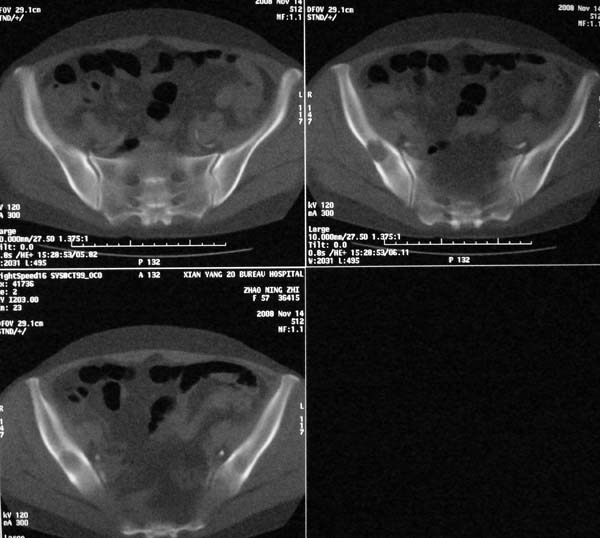

以下是引用dr.yang在2008-11-9 21:56:00的发言:[br]右肾上极占位?建议增强

以下是引用x-man在2008-11-9 22:30:00的发言:[br]建议先增强,右肾影明显增大,上极见边不清低密度肿块影,肿瘤待定.

以下是引用卜一在2008-11-10 8:09:00的发言:[br]建议先增强,右肾影明显增大,上极见边不清低密度肿块影,肿瘤待定.支持!另:第一次碎石是否肾受到损伤?合并感染?不知第一次碎石前是否做过彩超?

以下是引用dsl555在2008-11-9 23:57:00的发言:[br]建议先增强,右肾影明显增大,上极见边不清低密度肿块影,肿瘤待定. [br] [br]